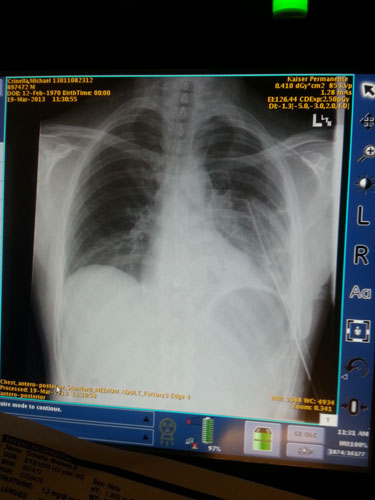

Today’s update on Handsome…the morning xray showed an unexpected increase in fluids on left lung

😦 They also found a mucus pocket thick like jelly. They put in another tube hoping to suck it out but it isn’t working. They will probably need to go in and clean out. Still wont let him eat or drink so he doesn’t leak anything through the tear in the esophagus. Doc thinks best case scenario he will be in hospital another week but it will be a long road to recovery. Handsome did get up and walk a little this morning. He sleeps a lot and is still having labored breathing due to the fluids around his left lung.

Handsome/Mike is in getting prepped for surgery which will begin any time now. It should be done between 12-1pm. The chest xray this morning looked much better. The antibiotics are finally working. Now need to fix the hole in the esophagus. Think happy thoughts for Handsome. I will let you know when surgery is over.